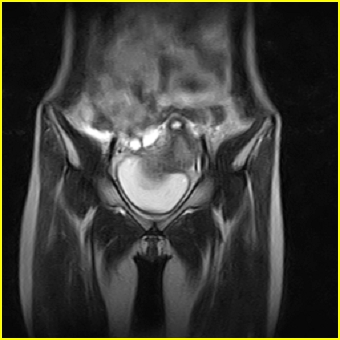

女、15岁、下腹疼痛2天,排尿困难1天。查体:处女膜闭锁,距处女膜约4至5cm处扪及一约5cm直径的圆形包块,张力较高,触痛明显、欠活动。b超提示子宫增大伴宫内增强回声团。

影像意见:子宫直肠陷凹积血。

更正影像意见:阴道积血。

处女膜闭锁,阴道积血

处女膜闭锁,阴道积血,子宫积血.

先天性处女膜闭锁,伴阴道积血,不除外先天性阴道粘液囊肿形成。

阴道积血,子宫积血.

子宫及阴道积血。

处女膜闭锁,伴子宫及阴道积血.